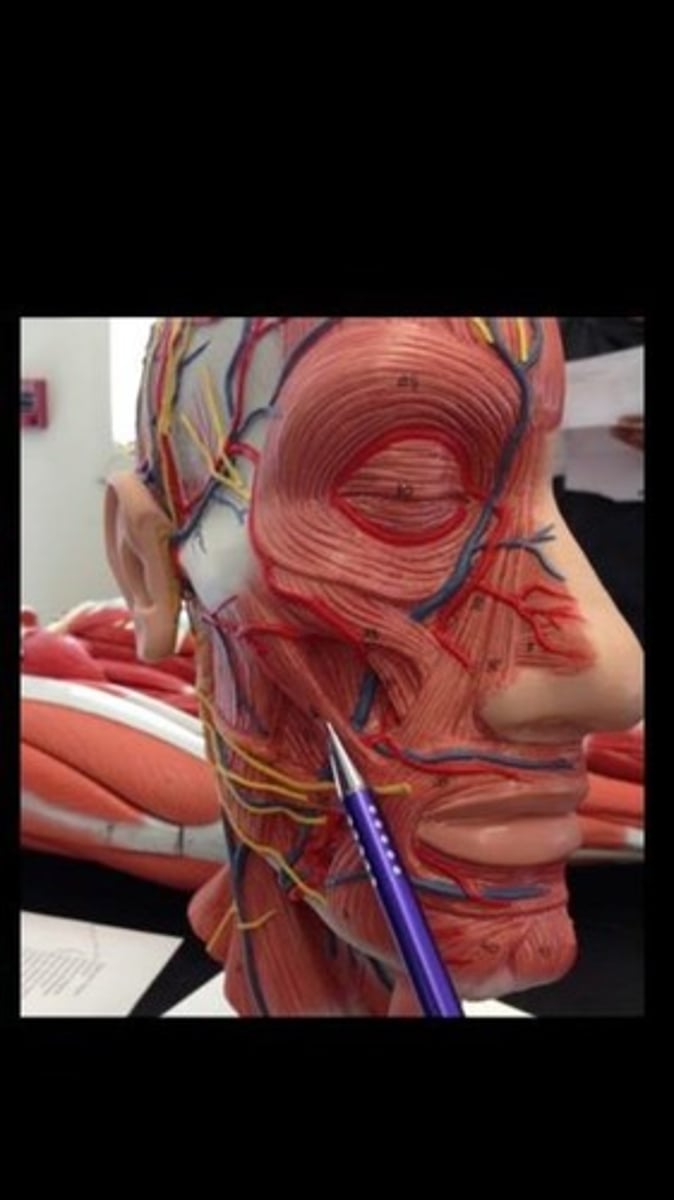

Occipitofrontalis

Orbicularis oris

Orbicularis oculi

Temporalis

Zygomaticus minor

Zygomaticus major

Buccinator

Masseter

Sternocleidomastoid